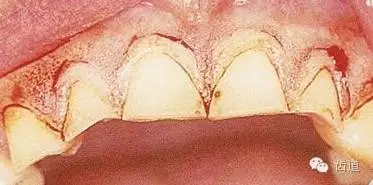

在臨床上,當(dāng)牙冠折斷或齲壞達(dá)齦下時(shí),會(huì)影響修復(fù)體的制作,常常因此而導(dǎo)致拔牙,如此時(shí)能將臨床牙冠延長(zhǎng),則會(huì)為制作良好的修復(fù)體創(chuàng)造條件,從而避免拔牙。臨床方法即為牙冠延長(zhǎng)術(shù)。

牙冠延長(zhǎng)術(shù)是通過手術(shù)方法,降低牙齦緣位置、暴露健康的牙齒結(jié)構(gòu),使臨床牙冠加長(zhǎng),從而利于牙齒的修復(fù)或解決美觀問題。

牙冠延長(zhǎng)術(shù)的原理是基于牙齦的生物學(xué)寬度。通常將齦溝底與牙槽嵴頂之間的恒定距離稱為生物學(xué)寬度,約為圓援 園源 皂皂,它的建立與穩(wěn)定是保證牙周組織健康的關(guān)鍵。單純的牙齦切除術(shù)只是把增生覆蓋于牙根斷面上的牙齦去除了,但不能恢復(fù)生物學(xué)寬度中的骨嵴頂上方的結(jié)締組織和結(jié)合上皮的附著位置,冠修復(fù)后如果冠邊緣侵犯了生物學(xué)寬度,作為一種保護(hù)機(jī)制,機(jī)體以骨吸收和牙齦增生的方式試圖重建,這樣將會(huì)導(dǎo)致慢性炎癥的長(zhǎng)期存在。牙冠延長(zhǎng)術(shù)通過手術(shù)的,降低齦緣的位置,去除相應(yīng)的牙槽骨,延長(zhǎng)過短的臨床牙冠,有利于修復(fù)或解決前牙美觀問題。